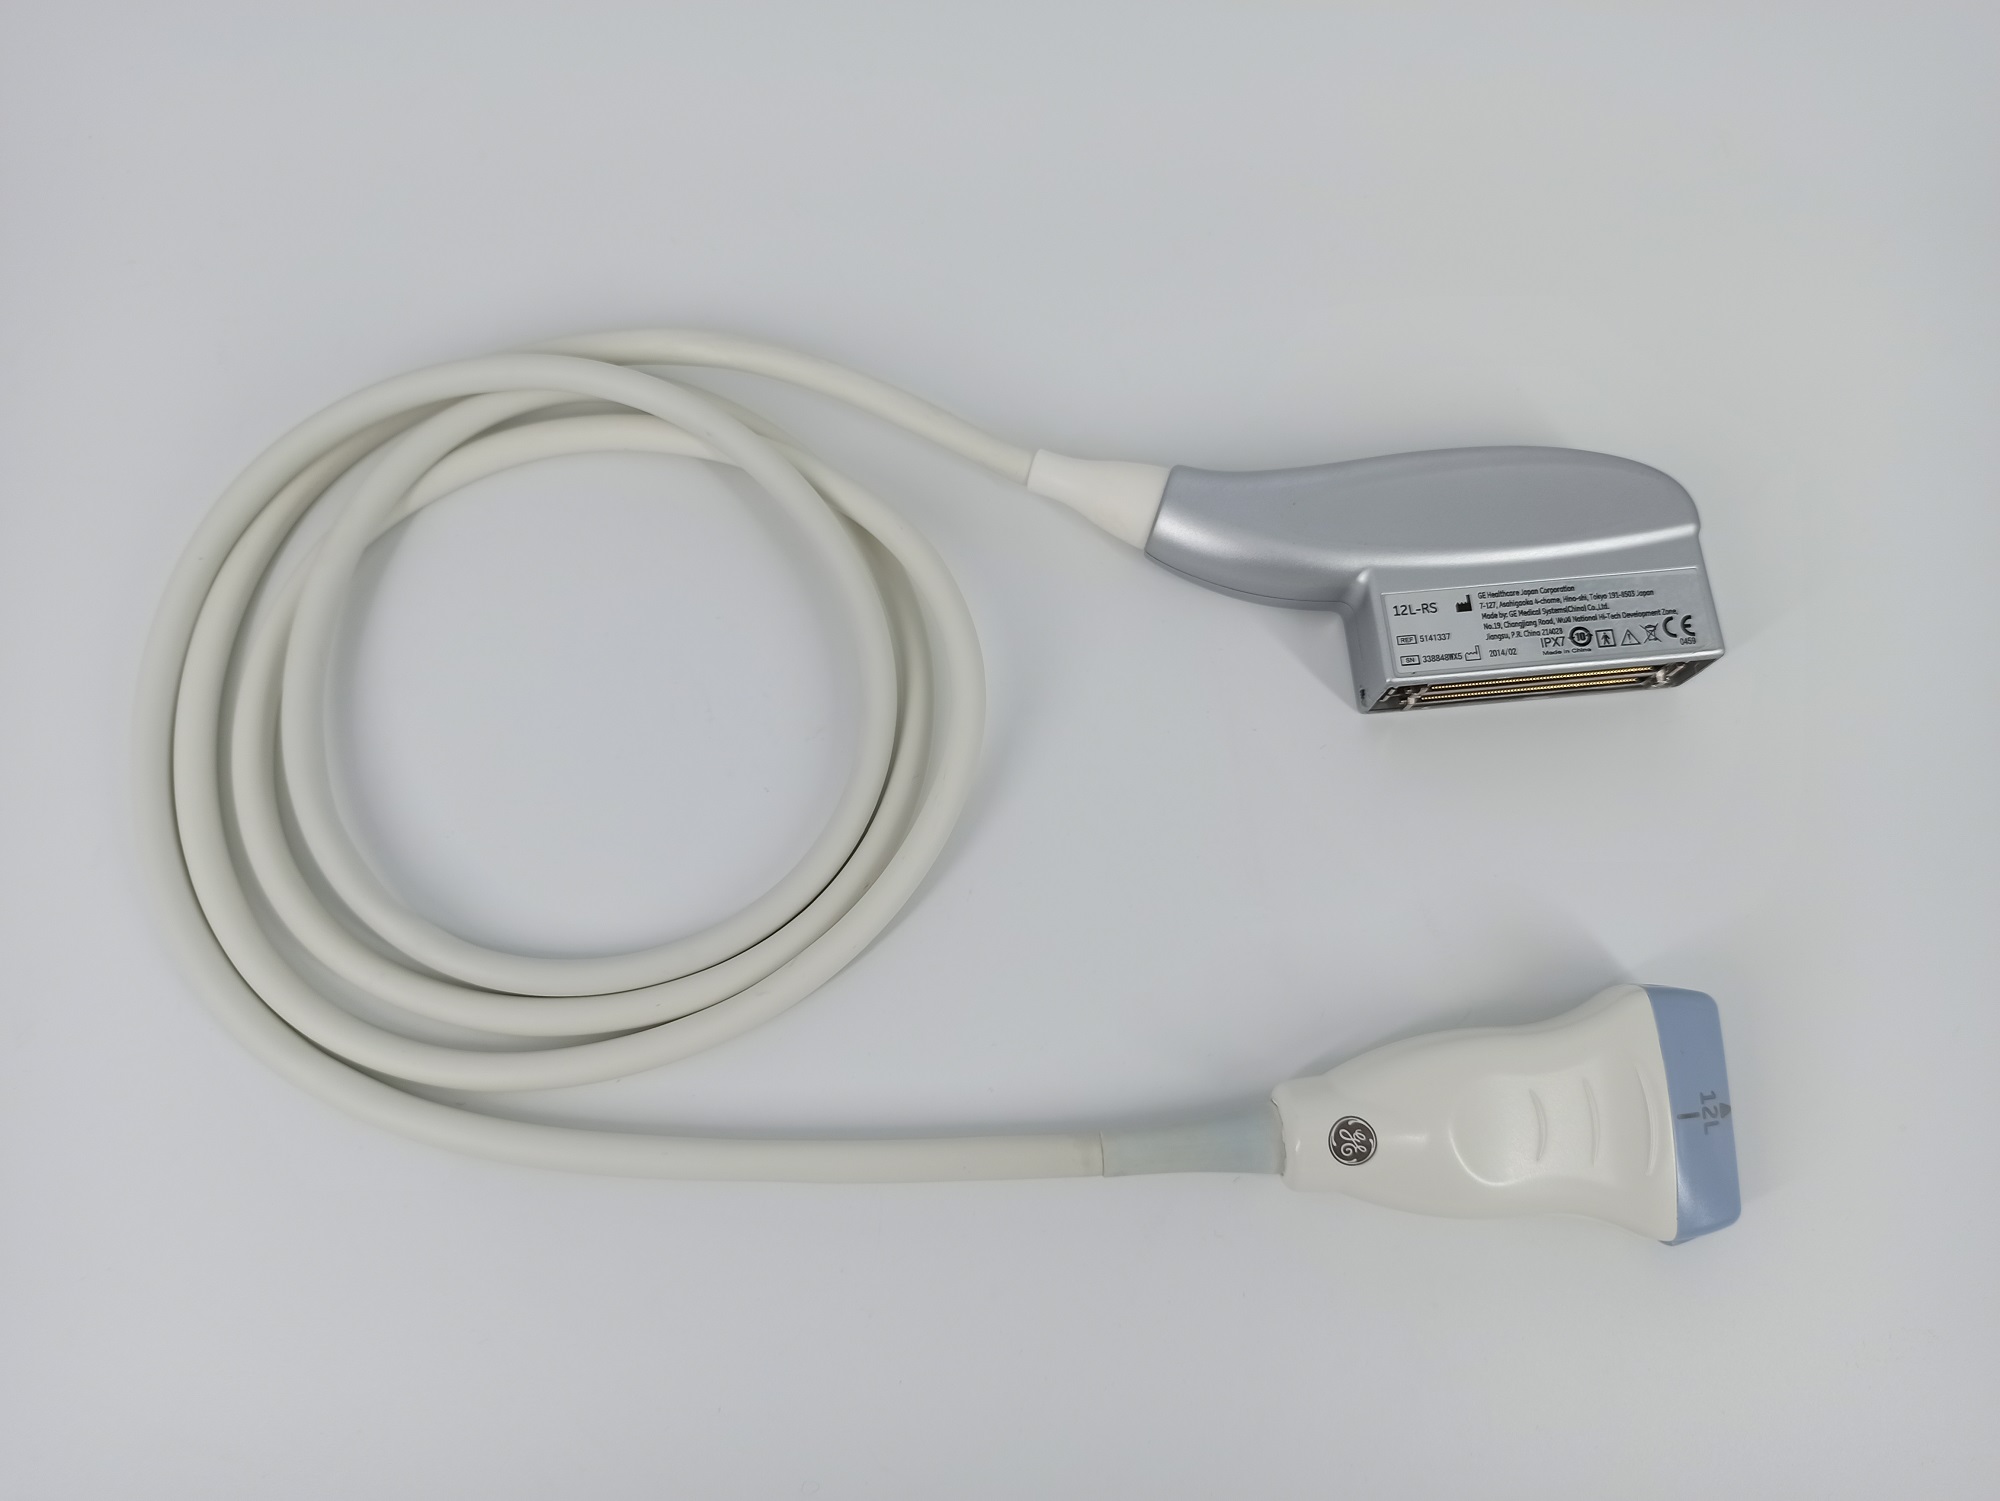

GE 12L-RS Vascular Linear Refurbished

GE Linear 12L-RS Vascular

Intended use

Vascular, Small Parts and Musculoskeletal

Frequency Range

13 – 4 MHz

System compatibility

LOGIQ, VIVID, VOLUSON

GE 12L-RS Vascular Linear

Frequency Range: 13 – 4 MHz

GE 12L-RS Vascular Linear for Vascular, Small Parts and Musculoskeletal

Compatible with GE Systems